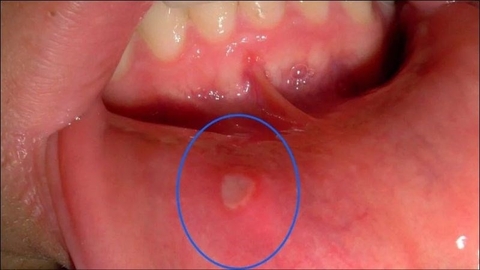

Mẹo Chữa Loét Miệng Từ Vị Thuốc y Học Cổ Truyền

Ngô thù du (Evodia rutaecarpa) là một loại thảo dược quý trong y học cổ truyền, đư...